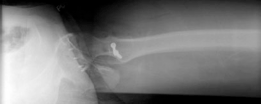

Standard preoperative imaging must include an anteroposterior (AP) pelvis, cross-table lateral, and false-profile view of the affected hip. These evaluate for dysplasia, impingement morphology (cam/pincer), and degenerative changes.

Magnetic Resonance Arthrography (MRA) is the gold standard for evaluating the capsuloligamentous complex. Extravasation of contrast anteriorly often delineates the size and location of the capsular defect. MRA also assesses labral integrity, chondral damage, and the viability of the femoral head. A 3D computed tomography (CT) scan is highly recommended to quantify femoral anteversion and acetabular version, as unrecognized osseous malorientation (e.g., severe femoral retroversion) will predispose the reconstruction to failure if not addressed concurrently with a derotational osteotomy.